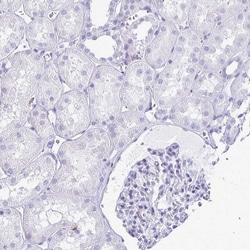

Invitrogen™ RTN1 Polyclonal Antibody

Immunogen sequence: SITPPSSGTE PSAAESQGKG SISEDELITA IKEAKGLSYE TAENPRPVGQ LADRPEVKAR SGPPTIPSPL DHEASSAESG DSEIELVS Highest antigen sequence indentity to the following orthologs: Rat - 85%, Mouse - 86%.

| Applications | Immunohistochemistry (Paraffin), Immunocytochemistry, Immunohistochemistry (Paraffin) |